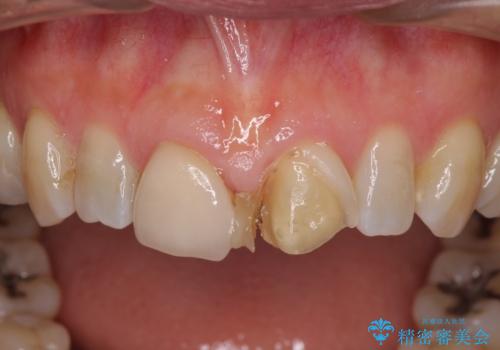

- 前歯のすきっぱを主訴にご来院された患者様です。他院でつめものやラミネートべニア(前歯の表面のみセラミックを貼り付ける)を行っていましたが、頻繁に外れることに悩まれており、クラウン(歯全体をセラミックがつつむ)をご希望されました。また、奥歯に大きな虫歯があり、歯が割れていたため、奥歯の治療も併せて行いました。

今回はまず欠けた場所を修復して見た目を回復させたのち、ラミネートべニアの仮歯をつくり、しばらく使用して考えて頂きました。メリットやデメリットを説明した結果、外れにくいセラミッククラウンをご選択頂きました。

右上の歯に関しても、大きな虫歯があったため、前歯の経過観察の間に治療を行いました。

ラミネートべニアのメリットは歯を削る量が少ない、デメリットは形態に限界がある、色の再現性に限界がある、外れやすい、境目から虫歯になりやすい等があります。

セラミッククラウンのメリットは比較的に色や形態が自由、外れにくい、デメリットは歯を削る量が多いのでしみる場合は根管治療が必要になる等があります。